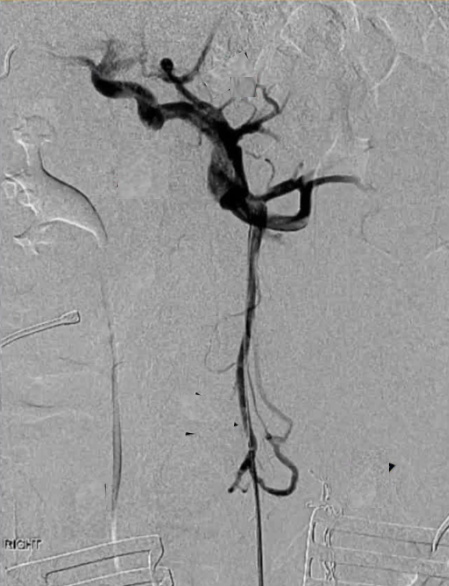

成功实现了经肝通路对门静脉系统的接入,但该接入方式显示出的是一个迂曲的肝周静脉网,且没有合适的肝内门静脉靶点用于进行经颈静脉肝内门体分流术(TIPS)的置入。因此,决定寻找其他途径接入门静脉系统,以便在 TIPS 术前进行再通处理。 通过有限的脐上剖腹探查术,在直视下对肠系膜上静脉的一个分支进行了插管,从而能够置入一个 6 号规格的鞘管。 随后通过该通道实现了对中央/肝内门静脉的直接再通。接着,从肝门静脉窦通道取出一个套管,将其置入肝内门静脉系统,从而能够从中肝静脉进行穿刺操作。 凭借这一通道,椎间盘源性疼痛的手术置入操作得以顺利完成。 患者开始使用克赛(lovenox),并在手术后 3 天出院。 该患者无需再次进行腹腔穿刺,但在经颈静脉肝内门体分流术(TIPS)术后 2.5 个月,因中再次央门静脉狭窄接受了 TIPS 血管成形术并置入了中央支架延伸段。 此病例展示了在慢性中央门静脉血栓形成等复杂情况下通往门静脉系统的其他通路,从而能够进行经颈静脉肝内门体分流术(TIPS)的实施,并对门静脉高压症进行治疗。 1) 传统的门静脉通路方法包括经颈静脉、经皮经肝以及经皮穿刺脾内通路等。 2)若经颈静脉、经肝和经脾的通路均无法使用,则可考虑采用经肠系膜静脉通路进行操作。 3)在腹腔镜手术辅助下或开腹SMV穿刺术,是一种适用于慢性门静脉再通手术的、安全的门静脉穿刺方法。 除了开腹肠系膜静脉或腹腔镜下肠系膜静脉穿刺,也有作者探讨经皮超声引导下穿刺的安全性